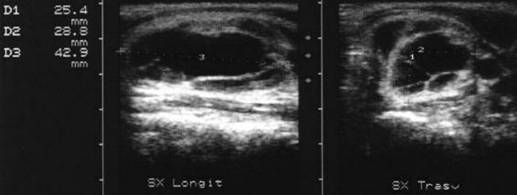

Femeie

de 23 ani. Chist mare (25x29x43mm, 16 cc) in lobul stang, marcant hipoecogen,

cu septe in interi si intarire posteriore.

Examen citologic: pseudochist coloid.

Aceeasi pacienta. Vascularizatie numai in periferie.